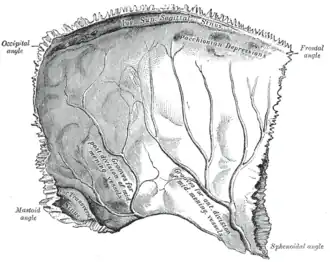

The arachnoid granulations may be lodged within granular foveae — small pits upon the inner surface of the cranial bones.[3][4]